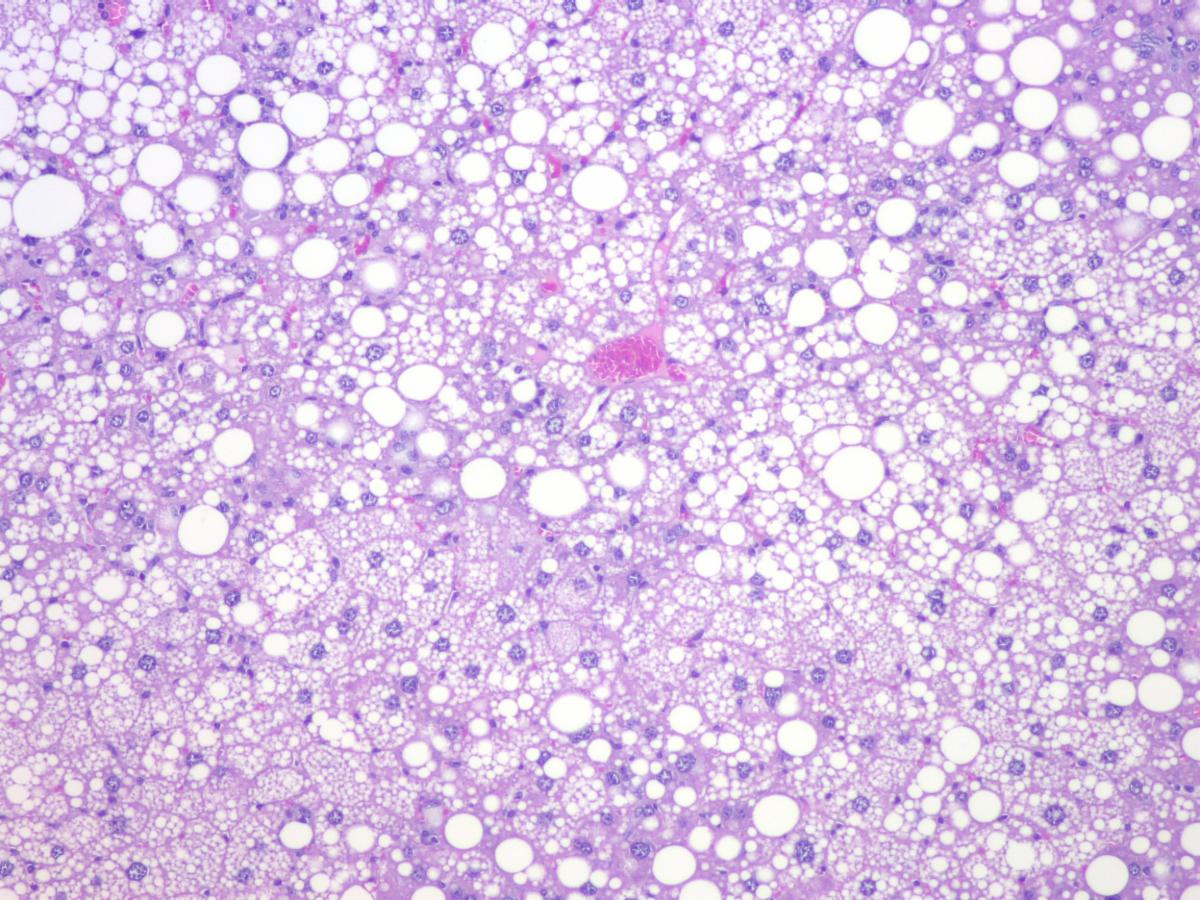

Metabolic Dysfunction-Associated Steatohepatitis (MASH), formerly Nonalcoholic Steatohepatitis (NASH), is a severe form of Nonalcoholic Fatty Liver Disease (NAFLD). There is a significant unmet need for new therapies to treat this debilitating disease. QPS has developed mouse models to support new drug development in this area.

QPS Model #1: Western Diet and Sugar Water-induced MASH Model

• Male C57BL/6J mice will be fed a Western diet and sugar water for 28 weeks. The treatment of vehicle, test article or reference drugs will occur from Week 16 to Week 28.

• Parameters to be evaluated: Body Weight, Serum Chemistry, Liver Weight, Liver histopathology (NAFLD activity score, liver fibrosis).